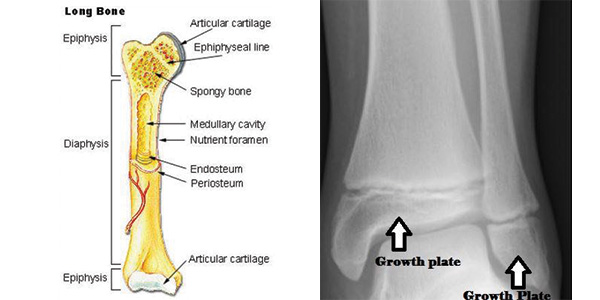

Os ossos dos filhotes estão rodeados por camadas de tecido cartilaginoso suave em desenvolvimento que se encontra em direção ao fim da maioria dos ossos longos. Estas áreas de cartilagem mole são conhecidas como placas de crescimento ou, mais tecnicamente, placas epifisárias.

O Cirurgião Escocês John Hunter estudou as placas de crescimento com grande detalhe no final do século XVIII. Os seus estudos sobre galinhas em crescimento revelaram que os ossos não se desenvolvem desde o centro para o exterior, mas que os ossos crescem ao longo à medida que novos ossos são gerados no final dos ossos longos, onde se localizam as placas de crescimento. .

Os estudos de John Hunter deram-lhe o apelido de “Pai da placa de crescimento” e as suas contribuições certamente ajudaram tanto a humanos como a animais. Como você pode imaginar, uma vez que as placas de crescimento são feitas de cartilagem mole e em desenvolvimento, eles são vulneráveis e podem ser bastante propensas. Para a lesão.

Para uma maior tranquilidade, considere que com um raio-X é possível ver se os ossos se fundiram ou não. Em um raio-X, o veterinário poderá determinar se a placa de crescimento se transformou em uma parte sólida e integral do osso, deixando o seu único traço de existência sob a forma de uma linha epifisária, como se vê na imagem da direita.